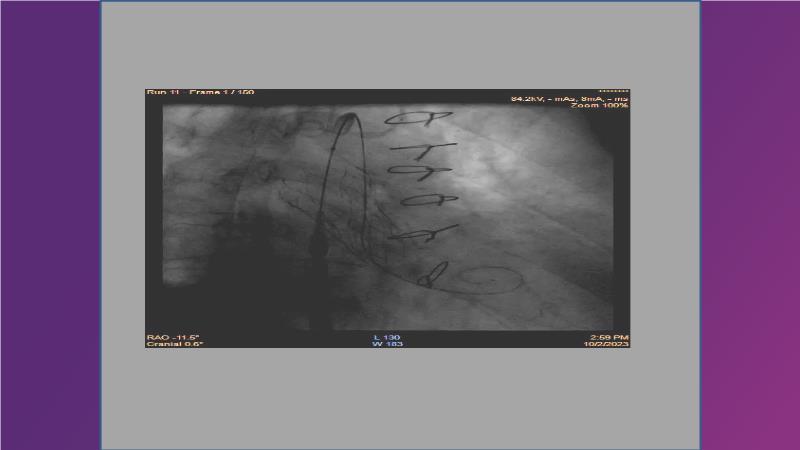

Gain expertise in selecting the appropriate TAVI device for achieving stable deployment in a 90-degree horizontal aorta. Discover techniques for ensuring smooth deliverability, particularly when navigating through tight and tortuous anatomies. Additionally, learn strategies to prepare for future coronary access, irrespective of the height of the left or right coronaries.

• To witness smooth deliverabilty even crossing tight and tortous anatomy

• To be ready for future coronary access regardless of the height of left or right coronaries